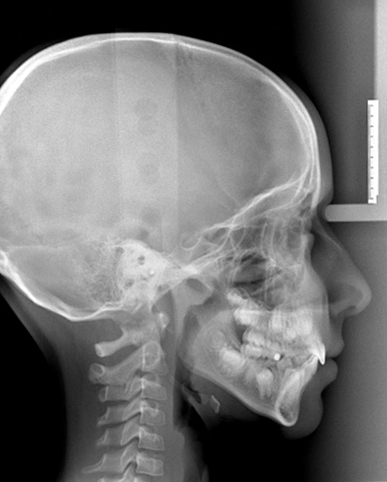

Teleradiografia Sirona